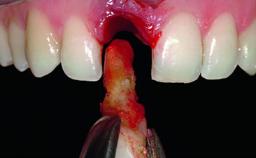

A healthy 38-year-old male patient was referred for replacement of a failing tooth-supported cantilever fixed dental prosthesis on teeth 11 and 21. The patient reported a history of trauma at 13 years of age that had resulted in the subsequent loss of tooth 11, as well as endodontic treatment of the adjacent abutment tooth 21. A metal-ceramic cantilever fixed dental prosthesis replacing tooth 11 had been provided by his general dentist several years after the loss of the tooth, with tooth 21 as the sole abutment. At the time of initial presentation, this restoration had been in service for over 20 years.

Bone Volume | Deficient horizontally, allowing simultaneous augumentation |